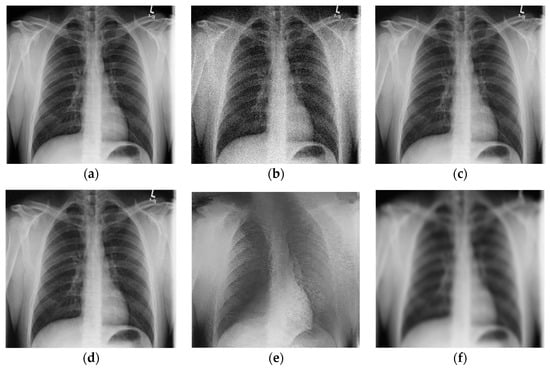

The results for the second test image (chest X-ray image with the resolution 2431 × 1782) are given in Figure 4. Namely, Figure 4a,b shows the noise-free and the noisy image (also corrupted with AWGN with σ = 25), respectively. Figure 4c–e present denoised images obtained using the proposed 2D LPA-RICI algorithm with quadrilateral, octagonal and hexadecagonal regions, respectively.

Figure 4.

Chest X-ray scan. (a) Original noise-free image; (b) Noisy image (AWGN with σ = 25); (c) Image denoised using the 2D LPA-RICI method (quadrilateral region, Г = 1.8, Rc = 0.8); (d) Image denoised using the 2D LPA-RICI method (octagonal region, Г = 1.8, Rc = 0.8); (e) Image denoised using the 2D LPA-RICI method (hexadecagonal region, Г = 1.8, Rc = 0.8); (f) Image denoised using Gaussian smoothing filters; (g) Image denoised using total variation denoising.

The PSNR results for denoised chest X-ray images are found in Table 3. As it can be seen from Table 3, the proposed 2D LPA-RICI method (as it was the case for the shoulder X-ray image) outperformed fixed size 2D filtering in all cases. Furthermore, the RICI based denoising outperformed Gaussian smoothing filters and total variation denoising when quadrilateral and octagonal regions were used.

Table 4 gives PSNR improvements for chest X-ray scan denoised using the 2D LAP-RICI method compared to noisy images and images denoised using the fixed size filtering, Gaussian smoothing filters and the total variation method, respectively. Namely, the LPA-RICI method enhanced denoised image quality, both visually and in terms of the PSNR, by up to 9.40 dB when quadrilateral regions were used, by up to 10.23 dB when octagonal regions were used and by up to 5.25 dB when hexadecagonal regions were used (when compared to the noisy image PSNR). It also outperforms fixed size 2D median filtering in all cases, increasing the PSNR by up to 7.51 dB. In addition, the 2D LPA-RICI method outperformed the Gaussian smoothing filters by up to 5.35 dB when quadrilateral and octagonal regions were used. Furthermore, it also outperformed the total variation denoising increasing the PSNR by up to 3.30 dB (in case of the adaptive 2D quadrilateral and octagonal regions).